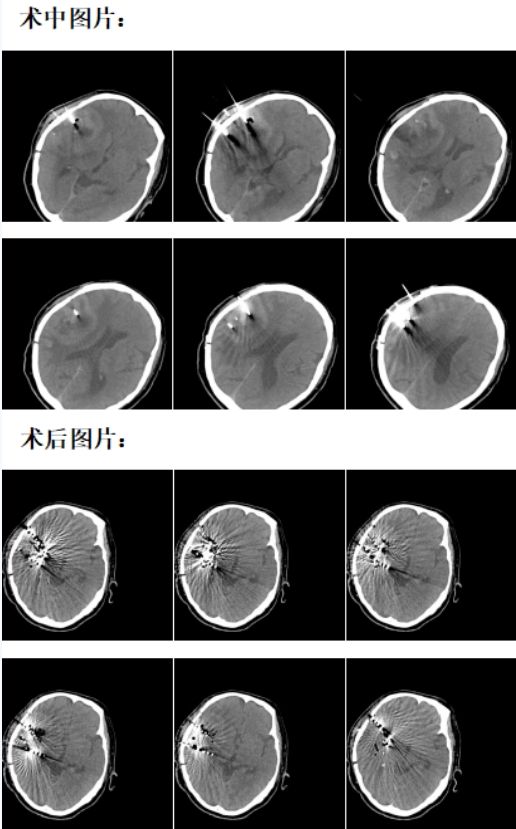

近日,淄博市第四人民医院放射科宓兵团队成功为一位脑胶质母瘤术后复发患者实施CT引导下的粒子治疗。

术后,患者生命体征平稳,两天后正常下床活动。

影像引导下的放射性粒子植入则可以到达局部根治性效果。一般外放疗的放射剂量为50-80GY,达不到肿瘤根治剂量,而放射性粒子植入治疗是将放射性粒子植入肿瘤内部进行近距离照射,肿瘤区域的放射剂量可达150-180GY,周围正常脑组织不受照射,适形度极好,疗效可以得到保证,所以成为无法手术,不适合手术及术后复发的胶质瘤患者治疗的重要手段。

由于颅脑粒子植入技术要求比较高,相对风险也较高,山东省内仅省立医院、青医附院等大型三甲医院开展此项业务。目前,淄博市第四人民医院放射科宓兵团队在省立医院李成利教授、青医附院胡效坤教授等支持帮助下,已成功开展十余例,均取得显著治疗效果,缓解患者症状,延长患者生命。